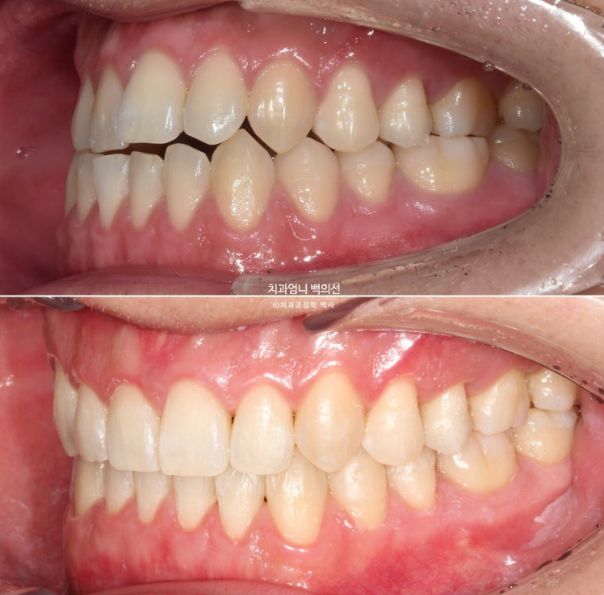

Now let’s compare before and after.

Treatment began in January 2023, and the time spent on arch expansion and waiting for bone to fill in was 6 months. The actual orthodontic treatment period while wearing Invisalign aligners was from July 2023 to March 2025, for a total of 1 year and 8 months.

The upper arch widened through the palatal expansion device

In the front teeth area, once the open bite and reverse bite were corrected, a stable bite was created.

Even after palatal expansion, the buccal corridor does not necessarily disappear.

The asymmetry of the chin appears to have been reduced compared with the beginning.